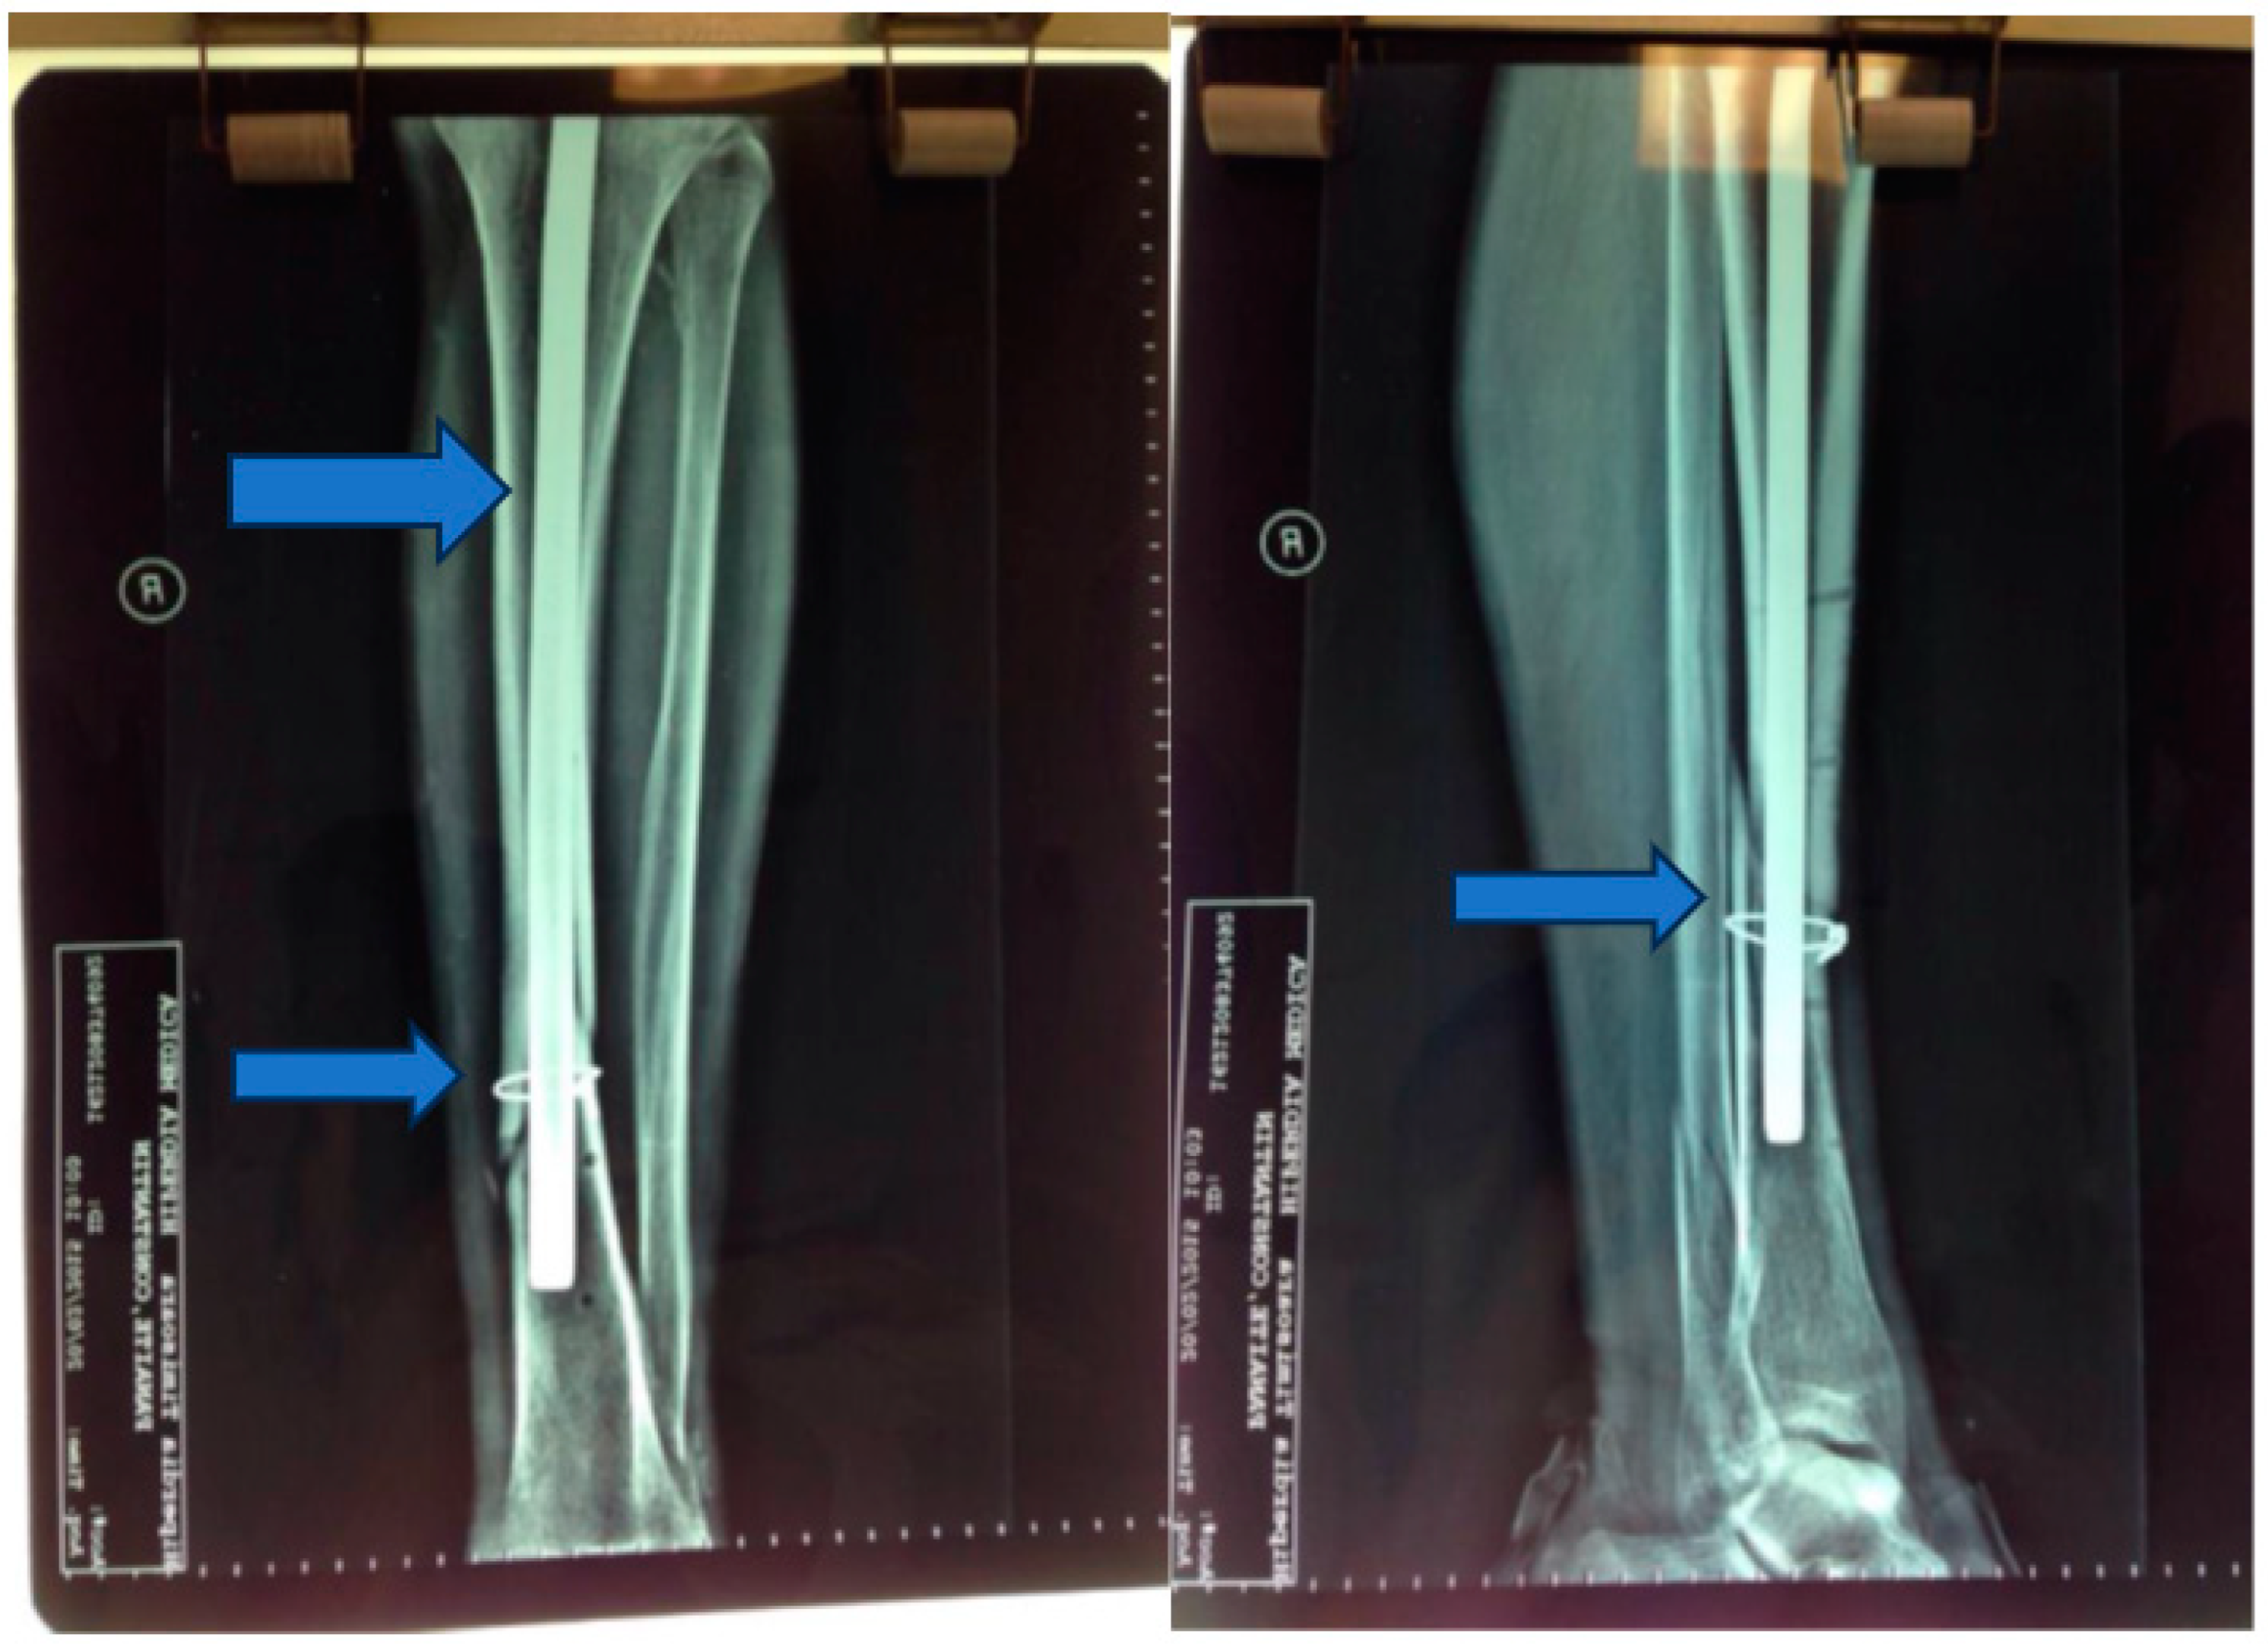

Stage 2: Infection control and debridement (Figure 4).

Objective: To address complications, prevent infection, and manage the wound dehiscence.

Methods: Implants from the initial surgery were removed, wide excisional debridement of necrotic tissue was carried out, pulse lavage was performed for wound cleansing, and osteoclasia was executed to facilitate bone healing. The peroneal malleolus was also manipulated, and a monoplane external fixation system was applied. Post-operatively, aspiration therapy using a vacuum pump was employed, and antibiotic therapy with vancomycin (2 g/day) for ten days was initiated based on the results of the antibiogram.

Figure 3. Postoperative X-ray—2 months.

Figure 4. Vacuum pump and ex fix.